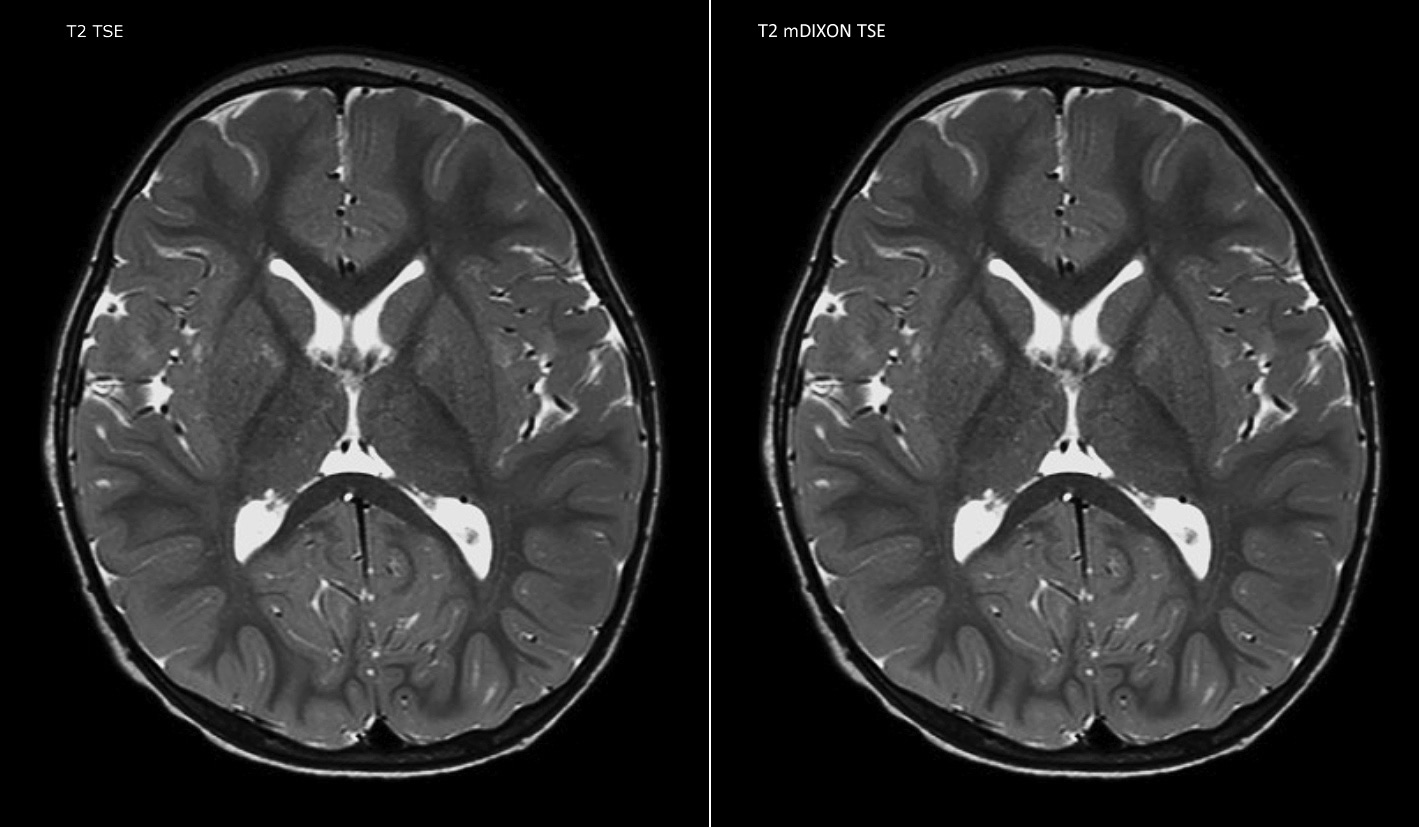

Philips mDIXON TSE is a two-point DIXON technique that separates water and fat signals, for time-efficient fat-free imaging, even in challenging neuro anatomy. “mDIXON TSE has been one of the most significant improvements in imaging sequences that we have utilized to date at PCH,” says Dr. Miller. “Its multi-parametric acquisition allows us to obtain fat suppressed images and equivalent non-fat suppressed T2 images all in the same sequence. In addition, prior methods of fat suppression could be artifactually corrupted by poor patient anatomy or poor operator application, but with mDIXON we now have a robust and reliable method of fat suppression.” Fat saturation is historically challenging at the ends of fields of view, especially in total spine imaging and in difficult patient anatomy such as the lower regions of the neck. “Due to the unique fat suppression capabilities of mDIXON, however, these challenges no long apply,” says Dr. Miller. “We routinely obtain homogeneous fat suppression under virtually all conditions. It has also led to some efficiencies by not having to repeat sequences because of that technical failure.”

“mDIXON TSE is most useful in patients with lesions or abnormalities in the soft tissues such as the face and neck, and for patients with contrast enhancing abnormalities that are mostly visible with fat suppression,” says Dr. Miller. “All our spine imaging now routinely contains mDIXON water-only T2 images, and this allows us to identify pathology that may be obscured by non-fat suppressed imaging such as injuries of the bone. And it’s not necessary to obtain additional standard TSE T2 images because the in-phase mDIXON images are equivalent to standard TSE T2 images.”